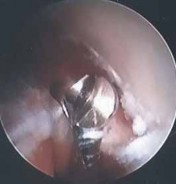

The capsule and tendon may be completely avulsed and retracted; this is classified as a type III lesion ( TECH FIG 2C).

The release of the muscle should begin at the site of degeneration or tear using a 4.5-mm incisor ( TECH FIG 2D).

- ### TECH FIG 2 • A. Type I lesion showing synovitis and fraying of the lateral joint capsule. B. Type II lesion showing linear tear of the joint capsule and the extensor carpi radialis brevis (ECRB) tendon near its insertion site.

- C. Type III lesion showing complete avulsion and retraction of the lateral capsule and ECRB tendon. D. Fatty degeneration of the ECRB tendon ( arrow ), which is overlying the ECRL muscle–tendon. E. A 4.5-mm shaver is used for the initial débridement of the ECRB, which is in close proximity to the capitellum ( C ) and radial head ( R ). F. Débridement of the pathologic ECRB tendon and capsule with healthy-appearing extensor carpi radialis longus superficial. G. A 4.0-mm abrader is the final step to decorticate the

- G lateral epicondyle. The ECRB release is complete.